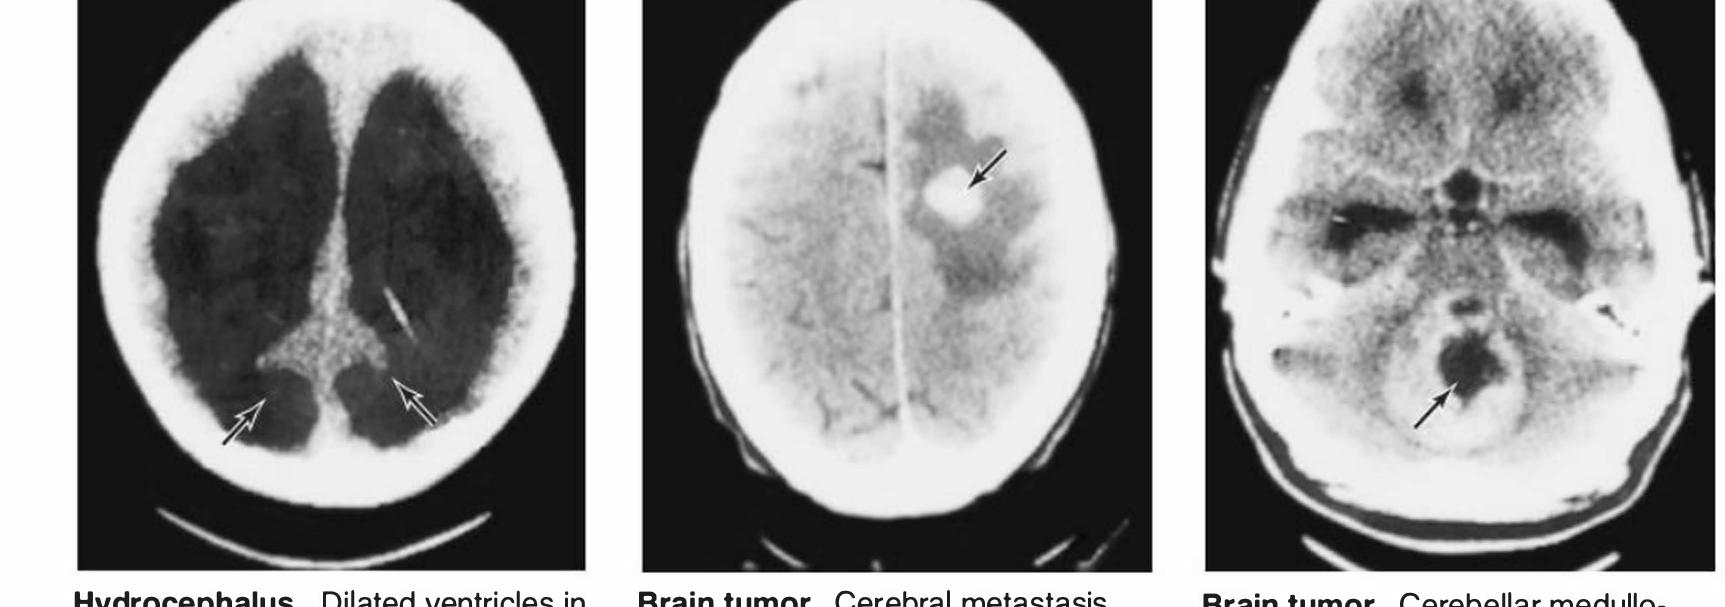

![The CT scanning apparatus rotates a narrow x-ray beam around the head. The quantity of x-ray absorbed in small vol- umes (voxels [volume elements, or units]) of brain, measuring approximately 0.5 mm? x 1.5 mm or more in length, is com- puted. The amount of x-ray absorbed in any slice of the head can be thus determined and depicted in various ways as pixels](https://figures.academia-assets.com/35806578/figure_337.jpg)